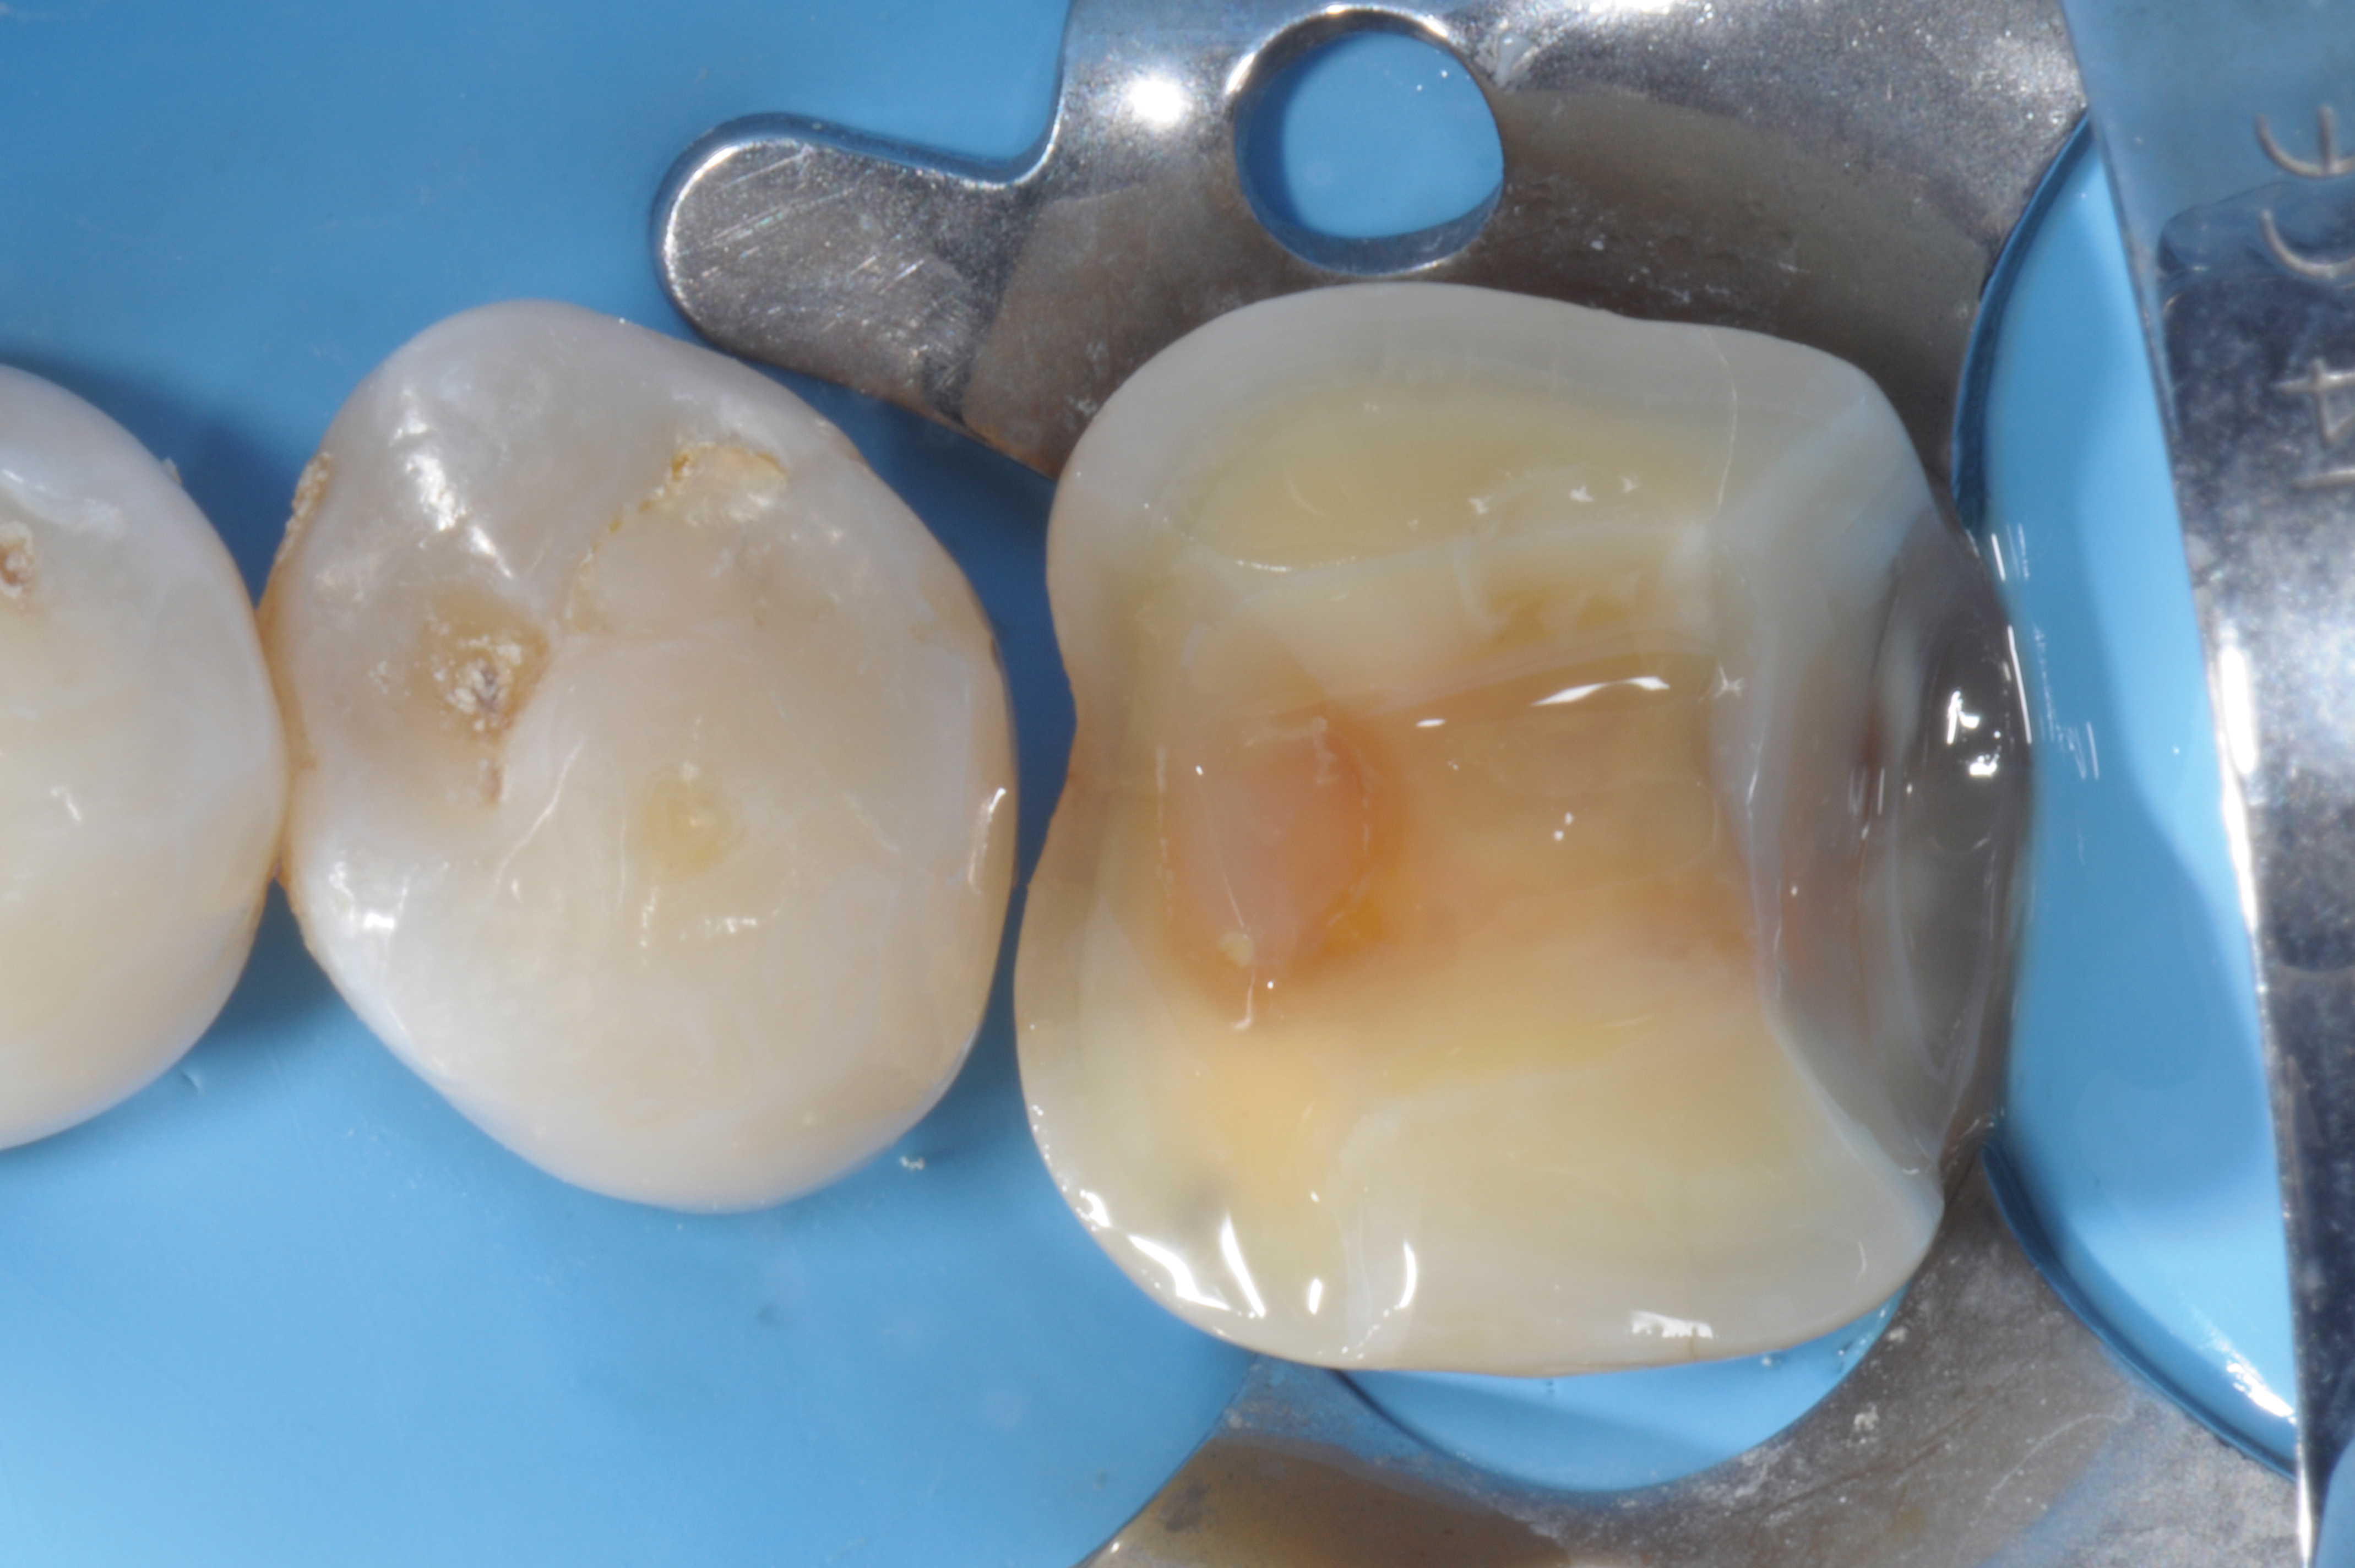

Fig 1. A mandibular first molar, with a fractured composite restoration: cavity preparation.

Figure 1